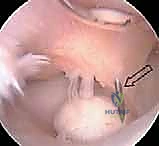

1. تنظير المرفق المتقدم بتقنية 4K (Elbow Arthroscopy)

تنظير المرفق هو إجراء جراحي دقيق يتم من خلال إحداث ثقوب صغيرة جداً (لا تتجاوز نصف سنتيمتر) حول المرفق. يتم إدخال كاميرا دقيقة وعالية الدقة (4K) وأدوات جراحية مجهرية للتشخيص والعلاج في آن واحد.

الإجراءات التي تتم عبر التنظير:

* إزالة الأجسام الحرة (Loose Body Removal): استخراج القطع العظمية والغضروفية المكسورة التي تسبح في المفصل وتسبب انغلاقه.

* تنظيف المفصل (Debridement): إزالة الأنسجة الملتهبة والغضروف التالف والهش لتجهيز بيئة صحية للشفاء.

* تقنية الثقوب الدقيقة / الكسور المجهرية (Microfracture): إذا كانت المنطقة المتضررة من الغضروف صغيرة إلى متوسطة، يقوم الدكتور هطيف باستخدام أداة دقيقة لإحداث ثقوب صغيرة في العظم المكشوف. هذه الثقوب تسمح بخروج الدم والخلايا الجذعية من نخاع العظم إلى سطح المفصل، مما يؤدي إلى تكوين "غضروف ليفي" يغطي المنطقة المتضررة ويعمل كوسادة بديلة.